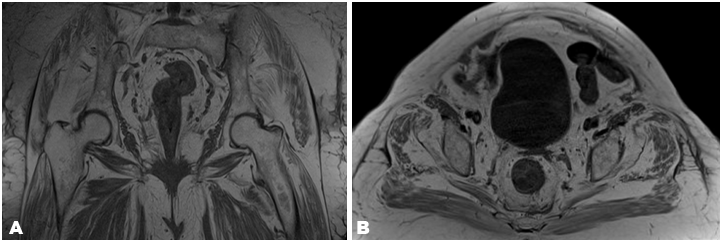

All identified Morel–Lavallée lesions were small (Figure 1) and (Figure 2). The right hip Morel–Lavallée lesion had a maximum width of 2.5 mm, and the left hip Morel–Lavallée lesion had a maximum width of 5 mm. Both collections above extend along the entire lateral aspect of the bilateral gluteus maximus. The third Morel–Lavallée lesion was superficial to the erector spinae muscles and extended from the level of the lumbosacral joint proximally with a maximum depth of 3.7 mm.

Figure 1: (A) Magnetic resonance imaging T1 turbo spin-echo (TSE) coronal cut, (B) Magnetic resonance imaging T1 turbo spin-echo (TSE) transverse cut.